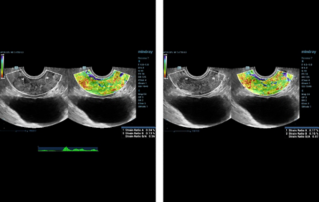

?? ?? ??? ?????(Endocavity volume convex array transducer)(DE10-3WU, Resona 7, ?????)? ??? ??? ???, ??? ?? 1/3 ?? ? ??(anterior vaginal wall)? ???? 18x14 mm ??? ?? ??(an ovoid-shaped formation) with a parietal fine suspension, ????? ??? ???? ??(non-displaced), ????,? CDI ??? ?? ?? ???? ????????. 3D ??? -? ??? ? ??(hyperechoic septa)? ?? ???? ??? ?? ??.

?? ??? ?? ???(Volumetric reconstruction)? ??? ??? ?? ??? ?? ??? ??? ? ??? ?? ??????? ??? ??? ??? ???.